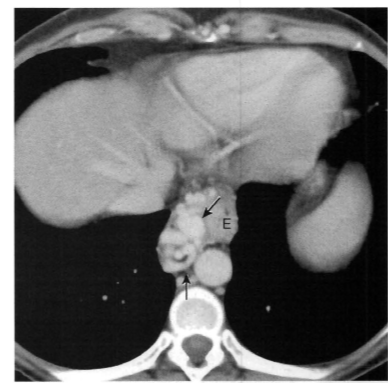

Homem, 57 anos, história de pancreatite crônica

Pseudoaneurisma da artéria mesentérica superior

Separação da camada média e da adventícia na parede da artéria (diferente do aneurisma, que seria a dilatação das três paredes do vaso). Pode ocorrer por aterosclerose, trauma, inflamação (como neste caso).

Pode estar associado à ruptura (pseudoaneurisma tem risco muito maior que de um aneurisma).